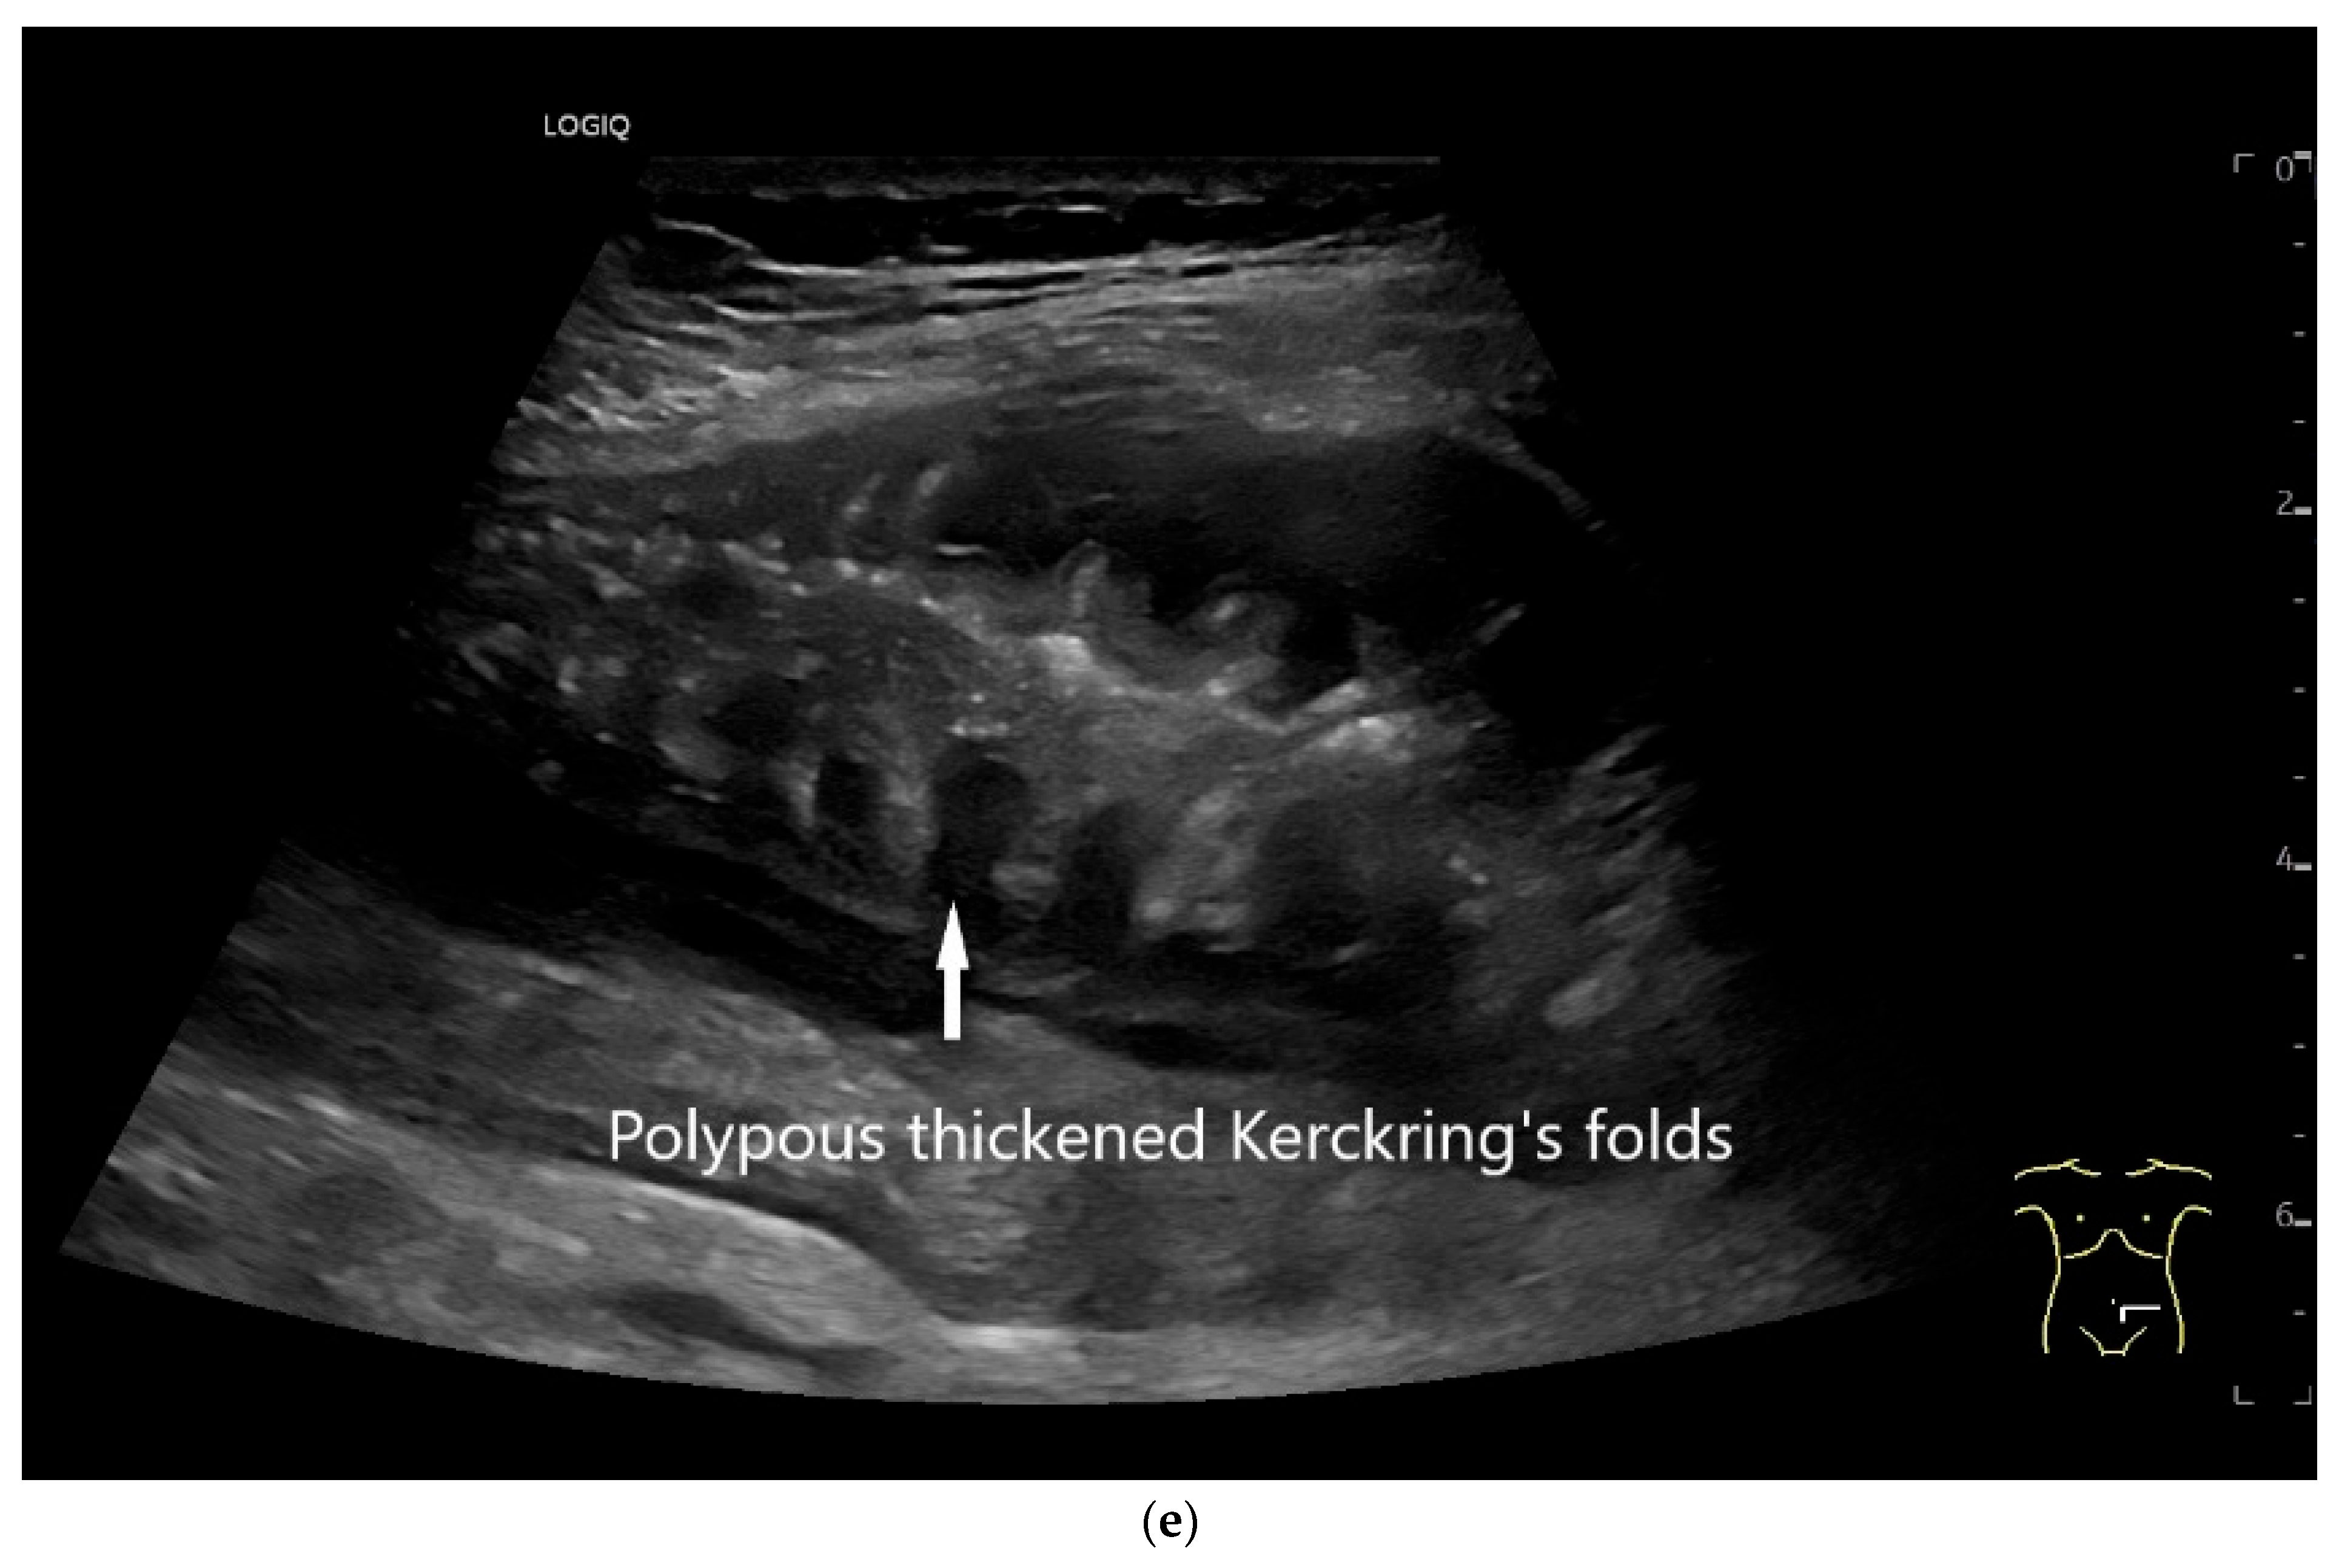

| Lymphoma | Very pronounced wall thickening with marked hypoechogenicity. Large regional and distant lymph nodes. Look for splenic infiltration. Tumor vessels on CDI and hyperenhancement on CEUS. Heterogeneous hyperechogenicity of the mesentery with walling of the mesenteric vessels. Multiple localizations are possible. |